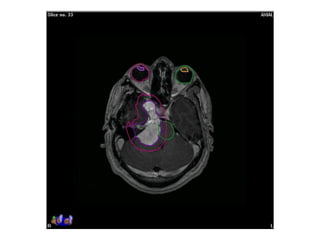

Response to treatment assessment

• ‘Lack of progression’ after conventional RT is considered response

• Increase in size as per RECIST criteria in considered progression

• High dose per fraction induce early regression in meningioma

• SRS (CyberKnife) induce early response with volume reduction

Pre-RT Post-RT: 6 mo

- No significant change in size of mass: stable disease

Response to treatmentassessment • ‘Lack of progression’ after conventional RT is considered response • Increase in size as per RECIST criteria in considered progression • High dose per fraction induce early regression in meningioma • SRS (CyberKnife) induce early response with volume reduction Pre-RT Post-RT: 6 mo - No significant change in size of mass: stable disease